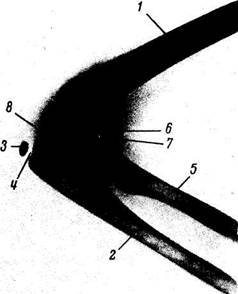

Рис. 43. Рентгенограмма плечевого сустава взрослого человека.

1 - ключица; 2 - суставная впадина лопатки; 3 — суставная щель плечевого сустава; 4 -клювовидный отросток; 5 — головка плечевой кости; б — большой бугорок;7 — суставная щель акромиально-ключичного сустава.

На задней рентгенограмме плечевого сустава (см. рис. 43) видна cavitas glenoidalis, имеющая форму двояковыпуклой линзы с двумя контурами: медиальным, соответствующим передней полуокружности cavitas glenoidalis, и латеральным, соответствующим задней полуокружности ее. В силу особенностей рентгеновской картины медиальный контур оказывается более толстым и резким, вследствие чего создается впечатление полукольца, что является признаком нормы («симптом четкого полукольца»). В старости и при некоторых заболеваниях становится подчеркнутым и латеральный контур, и тогда нормальный «симптом полукольца» cavitas glenoidalis заменяется патологическим «симптомом кольца».

Головка плечевой кости на задней рентгенограмме в своей нижнемедиальной части наслаивается на cavitas glenoidalis. Контур ее в норме ровный, четкий, но тонкий. Между cavitas glenoidalis scapulae и caput humeri видна рентгеновская щель плечевого сустава. «Рентгеновская суставная щель» плечевого сустава имеет вид изогнутого просветления, располагающегося между четкими контурами медиального (переднего) края cavitas glenoidalis и caput humeri. Чтобы определить вывих или подвывих плечевого сустава, очень важно знать нормальные соотношения между суставными поверхностями articulatio humeri. На рентгенограмме, сделанной в правильной задней проекции с вытянутой вдоль туловища конечностью, эти соотношения характеризуются тем, что нижнемедиальная часть головки наслаивается на cavitas glenoidalis и проецируется всегда выше нижней границы ее.